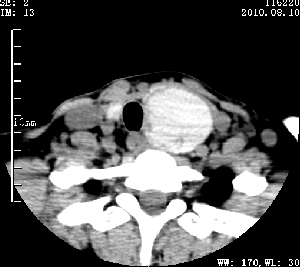

标题: CT28317:病人近几天无意间发现颈部肿块。 [打印本页]

标题: CT28317:病人近几天无意间发现颈部肿块。

甲状腺左叶局限性结节性甲状腺肿可能。建议增强扫描。

病变边界清楚,周围间隙清晰,甲状腺左叶(甲状旁腺?)肿大,右叶甲状腺腺瘤。

病变边界清楚,周围间隙清晰,左叶甲状腺肿大,右叶甲状腺小腺瘤。